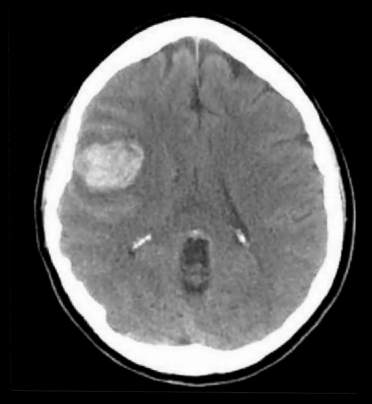

A

Hemorragia intraparenquimatosa por MAV ROTA

TAC: Se vería sangre en caso de rotura. HSA o IP